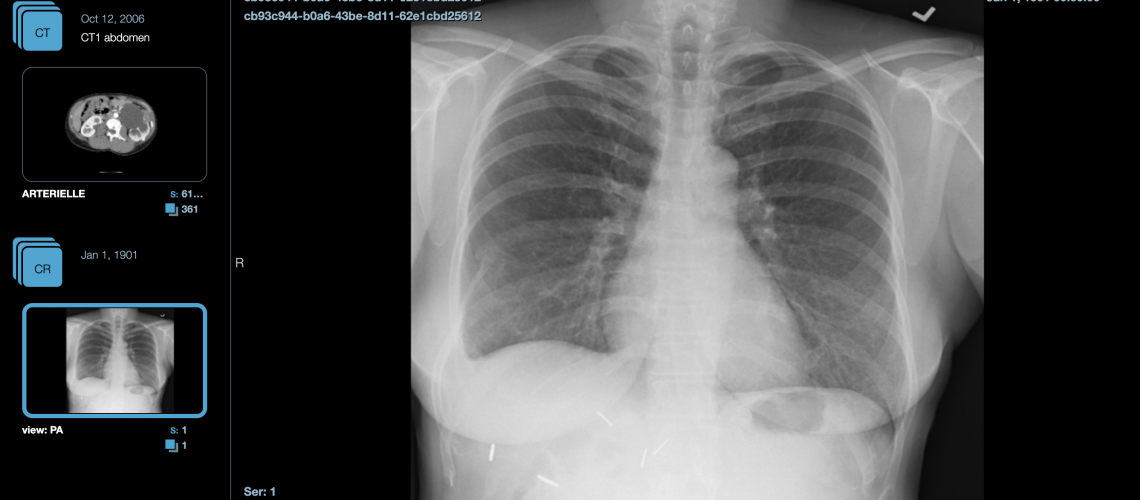

Aysel Afsar consiguió crear una aplicación mágica: el visor DICOM. En un momento tan aterrador, el visor DICOM contribuye, de forma sencilla, rápida y eficiente, como una herramienta de diagnóstico precoz e informe de exámenes de neumonía viral compatible con COVID-19 en varias regiones del mundo.

Permite a las organizaciones de salud ver imágenes DICOM, usando hardware de venta libre, el Hub NextCloud de código abierto y administrado, como nuestro BondiShare.

BondiShare y el visor DICOM permiten almacenar, recuperar, procesarfácilmente, y mostrando información de imágenes médicas. Nuestra plataforma controla los derechos de acceso a cualquier carpeta/archivo específico, tiene potentes etiquetas y servicio de flujo de trabajo, y ofrecemos copias de seguridad automatizadas, con un alto control de ciberseguridad y cumplimiento de la GDPR.